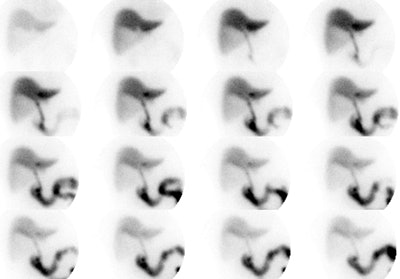

|

Gallbladder ejection fraction: To determine the gallbladder ejection fraction an ROI is drawn about the gallbladder and a time activity curve is generate. The GBEF is then determined. In this case the GBEF was 71% which is normal. Post CCK infusion cine images can be viewed by clicking on the image below (100KB). Case courtsey of Dr. Jamie Montilla. |